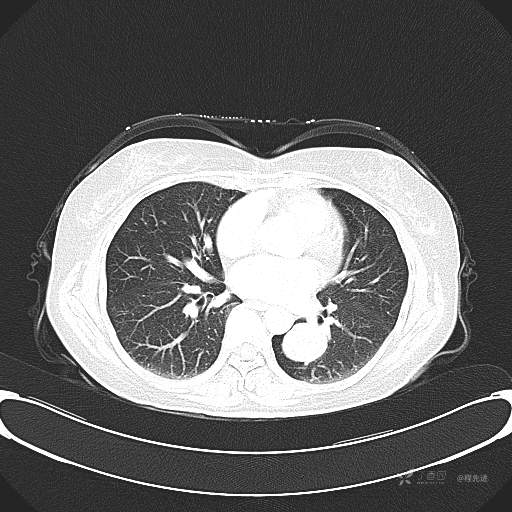

患者性别:女

患者年龄:57岁

简要病史:体检发现

CT增强

平扫CT值约40HU(未上传图像),增强后动脉期CT值约70HU,静脉期CT值约97HU。

肺硬化性血管瘤 (20)